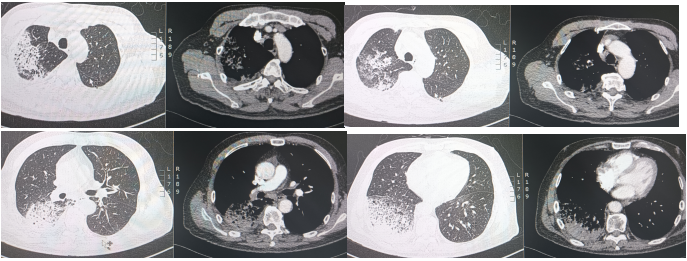

2024年8月21日急诊科胸部CT示:双肺散在炎症(右肺为著)(图1),入院后辅助检查示:白细胞计数10.09×109/L,中性粒细胞绝对数8.06×109/L,C反应蛋白119.34 mg/ml,降钙素原0.096 ng/ml,血清淀粉样蛋白>288.00 mg/L,红细胞沉降率测定96 mm/h,白介素-6 40.88 pg/ml;其余凝血功能、外周血淋巴细胞亚群、血生化、尿常规、粪便常规、心功能、肿瘤标志物、甲状腺功能、呼吸道病原体抗体、多重病原体核酸、支原体、衣原体核酸均未见明显异常。床旁气管镜示:右主支气管及各级支气管可见少许黄白色黏稠痰,以右肺下叶基底段为甚,予以灌洗后吸引并送检。左主支气管及各级支气管可见少许黄白色黏稠痰,以左肺下叶为甚,予以灌洗后吸引并送检。肺泡灌洗液(BALF)涂片、培养、GM试验、分枝杆菌检测、Xpert:(-);BALF NGS结果:流感嗜血杆菌(序列数15)。

入院后给予奈诺沙星0.5 g qd ivgtt、头孢他啶阿维巴坦2.5 g q8h ivgtt经验性抗感染治疗。治疗5天后复查相关指标:白细胞计数9.69×109/L,中性粒细胞绝对数7.31×109/L,C反应蛋白90.4 mg/ml,血清淀粉样蛋白>288.00 mg/L,红细胞沉降率测定94 mm/h;胸部CT:右肺上叶、下叶间质性炎症,左下肺小结节,炎性结节可能(图2)。提示病变无明显好转,告知家属病情后再次行气管镜检查,行病原学检查及病理检查,结果示:BALF涂片、培养、GM均阴性;BALF NGS回报:流感嗜血杆菌、烟曲霉。冷冻肺活检病理:(右肺下叶后基底段)肺组织急、慢性炎,肺泡腔内见纤维素样渗出物伴泡沫细胞聚集。免疫组化结果:CK7(+),TTF1(+),SMA(平滑肌+),NapsinA(+),PGM-1(+),Ki-67(+, 5%),P40(+),CD68(+)。考虑真菌感染不除外于8月31日加用伏立康唑0.2 g q12h ivgtt;醋酸卡泊芬净70 mg qd ivgtt抗真菌对症治疗。图2 2024年8月27日复查胸部CT较8月21日胸部CT无明显吸收9月5日再次复查相关指标:白细胞计数12.38×109/L,中性粒细胞绝对数9.27×109/L,C反应蛋白151.46 mg/ml,血清淀粉样蛋白>288.00 mg/L,红细胞沉降率117 mm/h。胸部CT:右肺散在间质性炎症,左下肺新发炎症灶,较前进展,左下肺小结节,范围较前增大(图3)。图3 2024年9月5日胸部CT右下肺炎症较8月27日进展,左肺出现新发炎症灶9月5日行MDT讨论,考虑感染继发机化性肺炎不除外,建议在目前抗感染治疗保驾下予中等剂量激素治疗,并严密动态观察相关指标。9月6日起治疗上加用甲泼尼龙琥珀酸钠80 mg qd ivgtt。治疗1周后(9月12日)复查相关指标:复查炎症标志物:白细胞计数16.47×109/L,中性粒细胞绝对数14.79×109/L,C反应蛋白11.08 mg/ml,血清淀粉样蛋白25.388 mg/L,红细胞沉降率28 mm/h。胸部CT:双肺散在间质性炎症(右肺为著),较前吸收(图4)。9月12日调整激素剂量为醋酸泼尼松片35 mg qd口服;9月19日患者无发热,无明显咳嗽、咳痰不适,予出院并嘱出院后维持醋酸泼尼松片35 mg qd口服,1周后每周减5 mg,减至20 mg后维持1周并复查胸部CT,根据胸部CT结果调整剂量。10月21日患者门诊复查胸部(图5),较前明显吸收,激素调整为醋酸泼尼松片10 mg qd,目前在持续随访中。治疗期间感染相关指标变化情况如图6所示。机化性肺炎(organizing pneumonia,OP)是一种肺组织修复过程,是以肺泡腔/管内有息肉状肉芽组织为病理特点,主要由成纤维细胞、肌成纤维细胞和疏松结缔组织基质构成[1]。同时与其他肺损害,如血管炎、淋巴瘤、肺癌、过敏性肺炎(hypersensitivity pneumonitis,HP)、嗜酸性粒细胞性肺炎(eosinophilic pneumonia,EP)、急性间质性肺炎(acute interstitial pneumonia,AIP)、非特异性间质性肺炎(nonspecific interstitial pneumonia,NSIP)或普通型间质性肺炎(usual interstitial pneumonia,UIP)关系密切。OP具有复杂的多态性,具有急性、亚急性和慢性多种形式。OP可以根据病因分为隐源性机化性肺炎(cryptogenic organizing pneumonia,COP)和继发性机化性肺炎(secondary organizing pneumonia,SOP)。COP与SOP在临床表现、影像表现和肺功能无明显差异[2],当有相关病因时诊断为SOP,当临床未发现相关潜在疾病时诊断为COP。OP的概念最早在肺炎链球菌的大叶性肺炎中被阐述,OP的发病机制目前主要认为肺泡上皮损伤,纤维蛋白渗出,导致成纤维细胞增生-肌成纤维细胞增生[3]。机化存在于多种肺损伤中,具有相同的本质,无论是局灶性还是弥漫性肺损伤,以成纤维细胞增殖为特征的机化是一种常见且几乎普遍的反应[4],机化被认为是对炎症渗出的反应和局限,很可能代表疾病的一个阶段,而不是独立的疾病。所以如果有确认感染的证据,虽然CT上发现有机化的特征,临床诊断OP往往是不必要的,除非这种机化是主要表现,而且改变了疾病进程。因此关注整体,将OP作为疾病的一个阶段,有利于建立对疾病的全息认识。OP没有特异的临床特征,患者可能出现发热、咳嗽、乏力、轻度呼吸困难、厌食症和体重减轻等,类似于流感[5],临床表现不特异。有些患者接受经验性抗生素治疗后往往无效,且疾病可能会迅速进展,导致严重的呼吸困难,甚至是ARDS,往往存在延误诊断。有文献报道大部分OP患者为不吸烟患者,肺功能主要表现为限制性通气障碍,也可表现为混合型和阻塞性通气障碍[6]。也有学者研究SOP患者有胸腔积液,而COP患者未报告胸腔积液[7]。因此,胸腔积液似乎与背景疾病有关,而与OP本身无关。OP的CT表现可以按照发生率分为典型和非典型模式[6],多数患者表现为典型模式,即多灶性实变,常被描述为斑片状肺泡阴影,一般位于下肺外周或支气管血管周围;实变可伴有支气管充气征,并可伴有散在的磨玻璃病变或小结节。而非典型的病变表现多样,可为磨玻璃影,也可为结节或肿块样表现、反晕征、铺路石征、小叶周围病变、线性和带状阴影以及网状结构。OP虽然有多种影像学表现,但均不特异,类似的表现同样可以出现在其他疾病中。例如,迁移性病灶可提示嗜酸性粒细胞性肺炎、感染、血管炎和复发性出血[8];弥漫性微小结节可见于过敏性肺炎、细支气管感染和炎症;反晕征可见于多种感染、非感染性肉芽肿异常,甚至原位腺癌[9]。因此诊断OP不能单纯依靠CT,需要结合临床和病理特征。目前针对OP的治疗,COP主要是以糖皮质激素为主[10],SOP需要兼顾原发疾病治疗及激素应用,因此我们需要尽早明确病理,及时治疗,减少不良预后。针对重症患者,尽早获取病理是必要的。此病例我们初步诊断为CAP,予抗感染治疗后疾病进展,及时行二次支气管镜冷冻肺活检+灌洗,同时通过mNGS及病理检查,最终被诊断为SOP,经激素抗炎治疗后症状好转,影像学提示病灶明显吸收。总之,OP在临床上并不少见,但由于其临床表现无特异性且CT表现多样,所以及时正确诊断OP罕见,诊断OP需要结合临床和病理特征,只有当OP成为主导性特征且干扰了疾病进程,才被冠以OP的诊断。针对初诊为肺炎的患者,当经验性抗感染治疗效果欠佳时,需要及时明确病原学检查及病理诊断,及时修改诊断及治疗路径,及时干预[11]。[1] CottinV,CordierJF. Cryptogenic organizing pneumonia[J]. Semin Respir Crit Care Med, 2012, 33(5): 462-475.